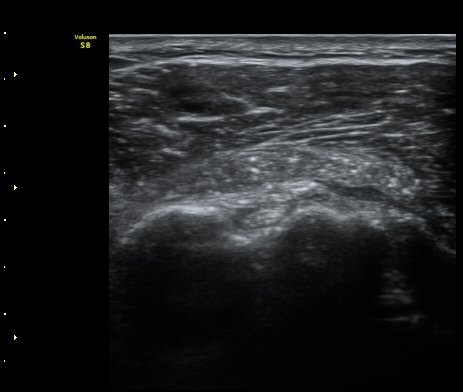

À̵ιڱ٠Ⱦ´Ü¸é°Ë»ç¿¡¼­ Á¡¾×³¶³» °í¿¡ÄÚ ¼®È¸È­ À½¿µµéÀÌ °üÂûµÊ(±×¸² 1, 2, 5)

¿ÜȸÀüÀÇ Á¦ÇÑÀ¸·Î °ß°©ÇϱٰÇÀÌ ¼öÆòÀ¸·Î °üÂûµÇÁö ¸øÇϰí À̵ιڱ٠ǥÃþ¿¡

¼®È¸È­ À½¿µÀÌ °üÂûµÊ(±×¸² 3)